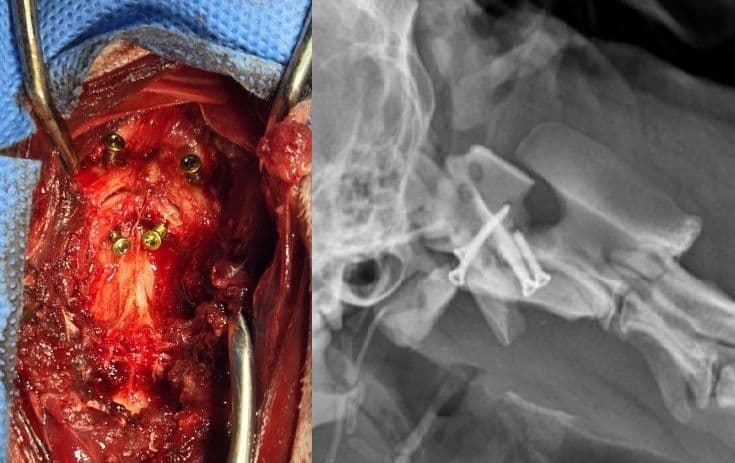

환축추아탈구(AAI) 교정술

고난이도 경추 수술